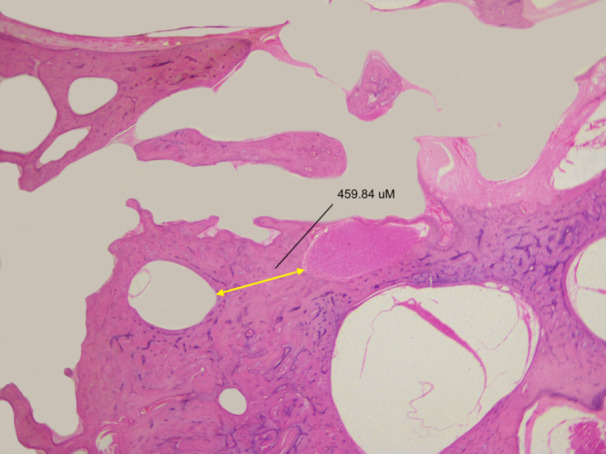

Study design: Normative data: Analysis of archival otopathological human temporal bone specimens and computed tomography (CT) scans. Clinical data: Case studies.

Methods: We measured the bony partition thickness between the FC-LSCC in human temporal bone otopathological specimens and CT scans. The clinical study involved a series of reviews of patients with FC-LSCC, presenting clinical data and CT images.

Results: The average thickness of the bony partition measured via CT was 0.6 mm ± 0.2 mm, whereas in otopathological specimens it was 0.56 mm ± 0.17 mm. We identified 34 patients with FC-LSCC dehiscence. The most frequently reported symptoms were hearing loss (44%), dizziness/vertigo (44%), and tinnitus (41%). Of the patients, 15 (44%) had more than 1 site of bone dehiscence and 21 (62%) had bilateral FC-LSCC dehiscence. We then identified 36 patients in whom only FC-LSCC dehiscences were found and provided characteristics for this population.